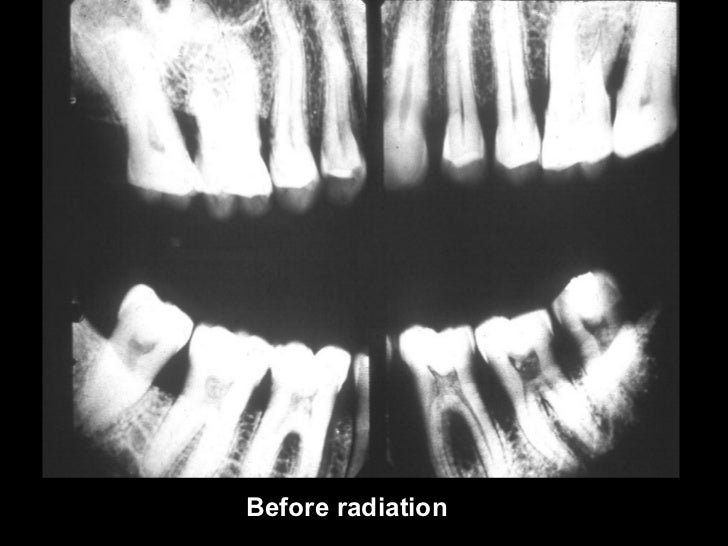

Radiation Caries Ppt . Dental caries is a preventable, reversible, multifactorial, complex biofilm disease that progresses with time. It describes the radiographic appearance of different types and stages of caries, including occlusal, proximal, facial, lingual, root surface, recurrent, rampant,. It is characterized by the interaction of bacteria,. Dental caries is an irreversible microbial disease that causes demineralization and destruction of tooth structure. Postradiation caries is a rapidly progressing and highly destructive type of dental caries. Dental caries is a dynamic continuum of tooth demineralization/neutrality/remineralization with a net demineralization initiating caries lesion. Visual examination and intraoral radiographs are still vital in diagnosis of dental caries.